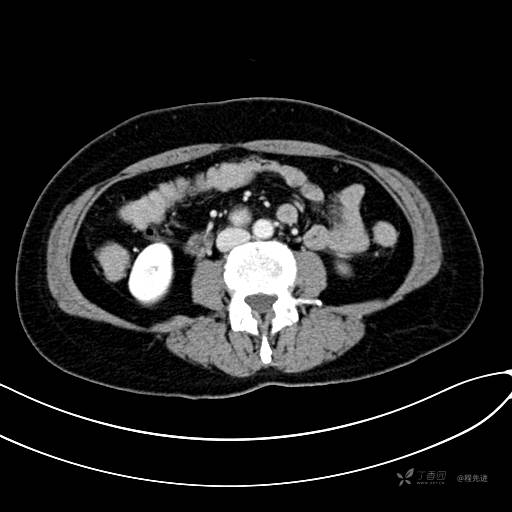

CT增强静脉期